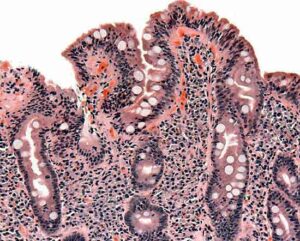

La malattia di Crohn è un’infiammazione cronica che può colpire qualunque tratto dell’apparato gastrointestinale, ma nel 90% dei casi interessa...

Sono 200 mila gli italiani colpiti dalle malattie infiammatorie croniche intestinali (Mici), il 30-40% è affetto dalla malattia di Crohn....